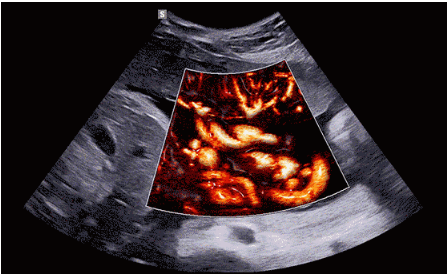

CrystalLive?是三星最新的超聲成像引擎,同時增強了2D圖像處理能力、3D渲染能力和彩色信號處理能力,能夠在復(fù)雜情況下提供出色的圖像性能,具備檢測外周血管、微循環(huán)血流的能力。

2D成像方面,Hera i10集成了包括ShadowHDR?、HQ-Vision?、ClearVision等多項具有三星“血統(tǒng)”的技術(shù),加強了圖像的陰影抑制、減少偽影、緩和模糊區(qū)。